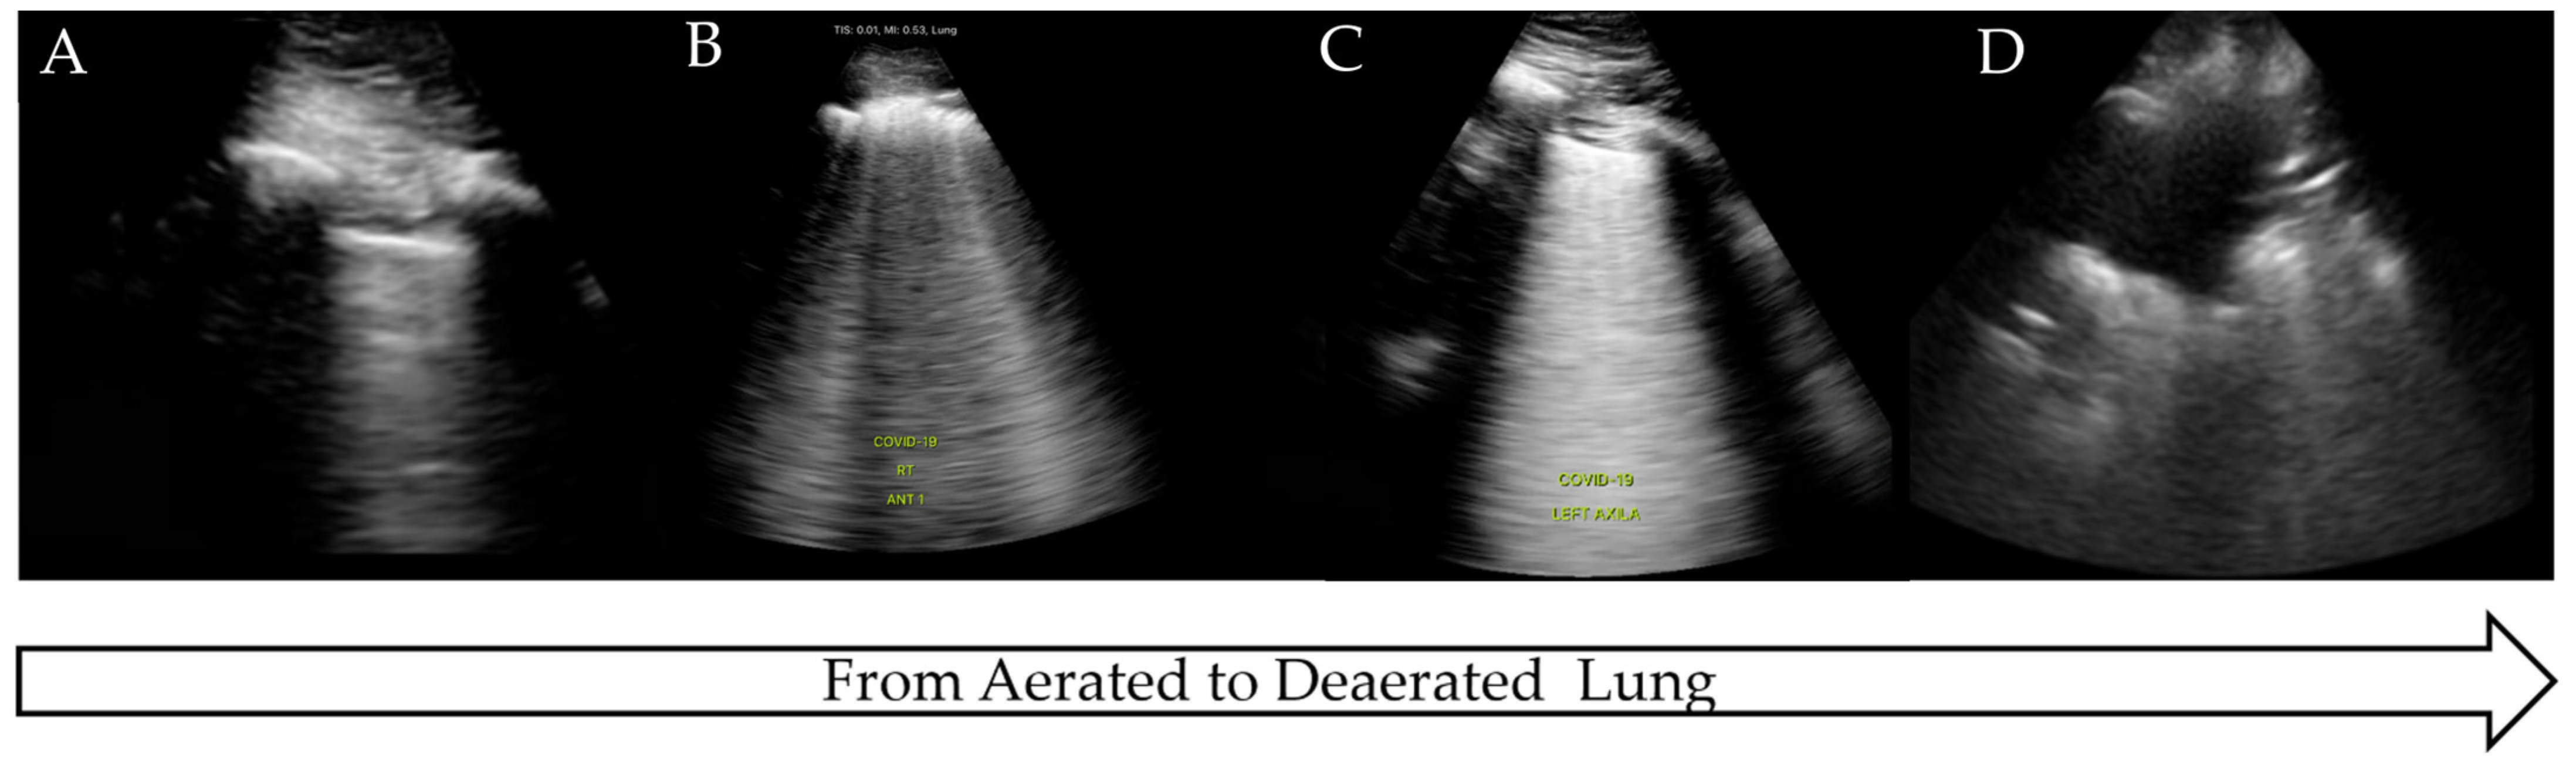

The COVID-19 pandemic presented an international health crisis that placed significant pressure on healthcare systems within intensive care settings. The wide range of presentations and severity of the disease required prompt diagnosis, treatment, and risk stratification. LUS was proposed as a method to aid in diagnosis, triage, and clinical management, being attractive due to its low cost, comparative ease of use, and rapid access compared to more traditional radiological techniques. COVID-19 has a predictable disease progression in the lung parenchyma, ranging from mild to severe disease and progressing from the distal regions of the lung with alveolar damage, interstitial thickening, and consolidation [45]. These pathological changes lead to distinctive LUS findings as the disease progresses from pre-disease (normal LUS scan of aerated lung) to critical illness (significant LUS abnormalities, completely de-aerated), similar to the findings in ARDS [45,46,47] (Figure 4).

Figure 4.

LUS findings on COVID-19 progression. (A) Normal aerated lung, (B) irregular pleural line with B-lines, (C) B-lines on >50% of image: ‘white lung’, (D) completely de-aerated collapsed lung.

Although COVID-19 has some distinctive features on LUS such as ‘moth eaten’ irregular pleura and B-lines, no single LUS finding is pathognomonic for COVID-19 and may be seen in other disease processes, as outlined. Therefore, LUS findings in COVID pneumonia, viral pneumonia/pneumonitis, and ARDS may overlap [48], and clinical correlation is often required. Due to the non-homogeneous nature of COVID-19 in the lung parenchyma, disease progression can be monitored over time, from confirmed infection to mild or severe illness, and finally to recovery.